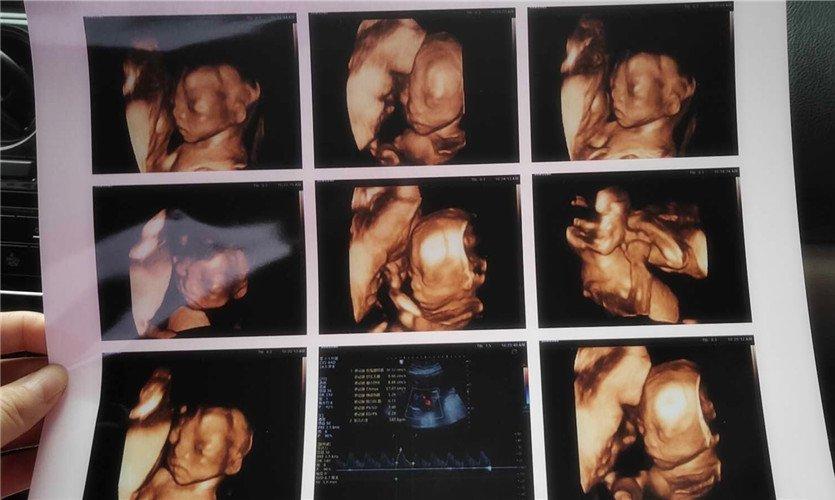

四維彩超是一種先進的醫(yī)學(xué)影像技術(shù),通過實時觀察胎兒在母體內(nèi)的活動情況,為醫(yī)生提供了豐富的診斷信息,在四維彩超下,我們可以清晰地觀察到胎兒的蛋蛋(睪丸)的形態(tài)、位置和大小等特征,胎兒蛋蛋是男性生殖系統(tǒng)的重要組成部分,對于胎兒的生長發(fā)育具有重要意義。

四維彩超下胎兒蛋蛋的樣子

在四維彩超下,胎兒蛋蛋呈現(xiàn)出特定的形態(tài)和外觀,通常情況下,胎兒蛋蛋呈現(xiàn)出圓形或橢圓形,表面光滑,內(nèi)部回聲均勻,隨著胎兒的發(fā)育,蛋蛋會逐漸增大,并呈現(xiàn)出明顯的性別特征,醫(yī)生可以通過四維彩超技術(shù),對胎兒蛋蛋的大小、形態(tài)和位置進行評估,以判斷胎兒生殖系統(tǒng)的健康狀況。

胎兒蛋蛋的發(fā)育是一個復(fù)雜的過程,受到多種因素的影響,在胎兒發(fā)育的早期階段,蛋蛋位于腹腔內(nèi),隨著胎兒的生長發(fā)育,蛋蛋逐漸下降至陰囊,這個過程受到激素、遺傳和環(huán)境等多種因素的影響,在四維彩超的觀測下,我們可以實時了解胎兒蛋蛋的發(fā)育過程,及時發(fā)現(xiàn)異常情況并采取相應(yīng)的治療措施。

四維彩超技術(shù)在評估胎兒蛋蛋發(fā)育方面具有重要意義,通過四維彩超,醫(yī)生可以實時觀察胎兒蛋蛋的形態(tài)、位置和大小等特征,了解胎兒生殖系統(tǒng)的發(fā)育情況,四維彩超還可以幫助醫(yī)生發(fā)現(xiàn)可能的異常情況,如睪丸未降、睪丸囊腫等,為及時采取治療措施提供依據(jù)。